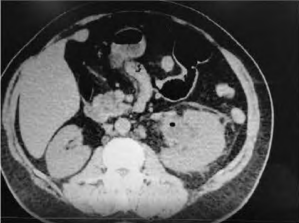

Paciente do sexo feminino, com 59 anos de idade, diabética e hipertensa, apresenta-se à emergência com dor lombar do lado esquerdo e febre, associadas a náuseas e vômitos. Foi realizada a tomografia de abdome e pelve, sem contraste, que é apresentada a seguir:

Fonte: Arquivo Pessoal.

O diagnóstico que se impõe nesse caso é: